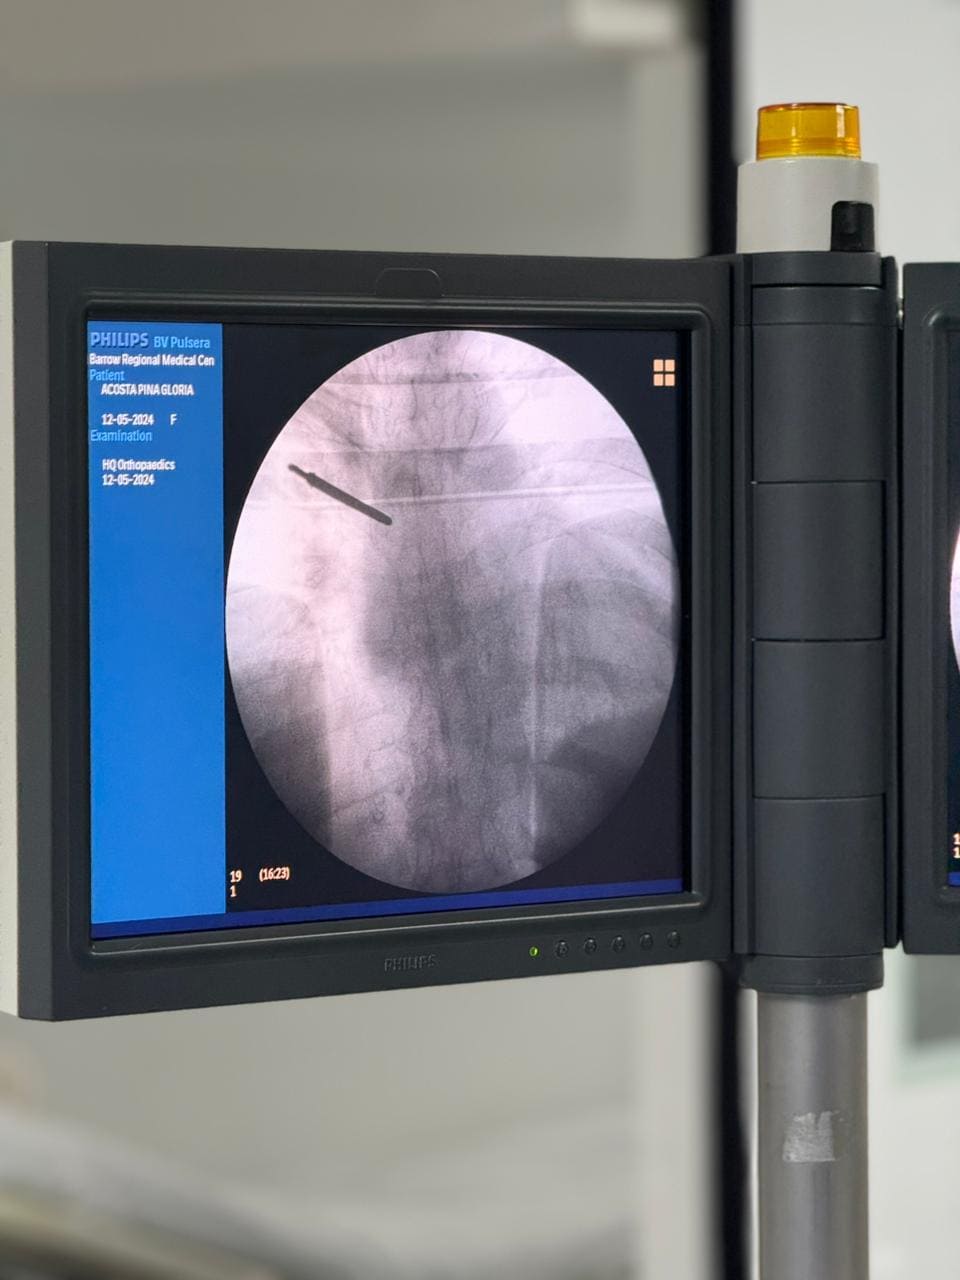

Técnica: Uso de sistemas de imágenes en tiempo real para colocar implantes con precisión. Beneficios: Mayor seguridad en procedimientos complejos. Menor riesgo de errores en la colocación de tornillos o placas. Mejora la estabilidad de la columna.